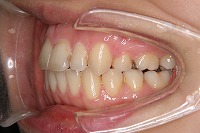

25歳6ヵ月

右

上の前歯が出ている事を主訴に来院された、23歳2か月の女性です。診断「下顎骨の後方回転による骨格性上顎前突で開咬を伴う」上顎は両側第1小臼歯、下顎は抜歯をせず治療を行いました。